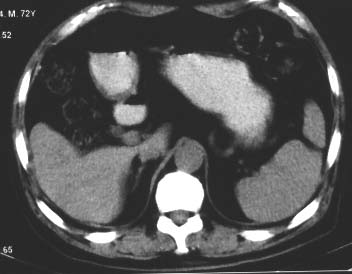

男 56 腹部不舒

典型肝硬化:1、肝各叶大小的比例失常;2、肝表面明显凹凸不整,边缘变钝;3、肝实质密度一般与正常肝无明显改变;4、肝裂增宽;5、门静脉增宽,脾静脉扩张扭曲;6、脾脏虽然不大,但不是所以肝硬化的脾脏都增大。

典型肝硬化:1、肝各叶大小的比例失常;2、肝表面明显凹凸不整,边缘变钝;3、肝实质密度一般与正常肝无明显改变,但肝右叶似可见再生结节影;4、肝裂增宽;5、门静脉增宽,脾静脉扩张扭曲;6、脾脏增大. 脾脏大小的标准有:1脾脏的左右径(大于5个肋单元) 2脾脏的宽度 3脾脏的上下径(超过肝下缘) 请参考.

典型肝硬化:1、肝各叶大小的比例失常;2、肝表面明显凹凸不整,边缘变钝;3、肝实质密度一般与正常肝无明显改变,但肝右叶似可见再生结节影;4、肝裂增宽;5、门静脉增宽,脾静脉扩张扭曲;6、脾脏增大.

典型肝硬化:1、肝各叶大小的比例失常;2、肝表面明显凹凸不整,边缘变钝;3、肝实质密度一般与正常肝无明显改变,但肉眼观察与脾胀密度低或等密度;4、肝裂增宽;5、门静脉增宽,脾静脉扩张扭曲;6、脾脏增大.

典型肝硬化:1、肝各叶大小的比例失常;2、肝表面明显凹凸不整,边缘变钝;3、肝实质密度一般与正常肝无明显改变,4、肝裂增宽;5、门静脉增宽,脾静脉扩张扭曲;6、脾脏增大.

影像表现上基本符合肝硬化,但肝缘还算光整,脾也不大<脾下缘低于肝下缘不能作为判断脾大的标准吧>胃底静脉曲张也不明显,还是先结合病史吧,会不会先天就这样呢.